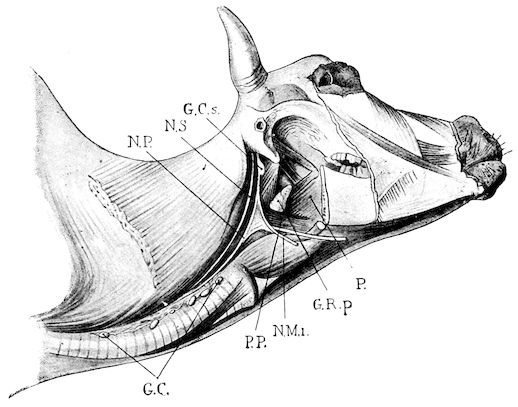

| I. | EXAMINATION OF THE RESPIRATORY APPARATUS | 311 | ||

| II. | NASAL CAVITIES | 319 | ||

| Simple coryza | 319 | |||

| Gangrenous coryza | 320 | |||

| Tumours of the nasal cavities | 325 | |||

| Purulent collections in the nasal sinuses. Nasal gleet | 326 | |||

| Purulent collections in the frontal sinus | 327 | |||

| Purulent collections in the maxillary sinus | 329 | |||

| Œstrus larvæ in the facial sinuses of sheep | 330 | |||

| III. | LARYNX, TRACHEA AND BRONCHI | 333 | ||

| Laryngitis | 333 | |||

| Acute laryngitis | 333 | |||

| Pseudo-membranous laryngitis | 333 | |||

| Tumours of the larynx | 335 | |||

| Bronchitis | 336 | |||

| Simple acute bronchitis | 337 | |||

| Chronic bronchitis | 337 | |||

| Pseudo-membranous bronchitis | 339 | |||

| Verminous bronchitis in sheep and cattle (Husk, hoose, etc.) | 340 | |||

| IV. | LUNGS AND PLEURÆ | 343 | ||

| Pulmonary congestion | 343 | |||

| Simple pneumonia | 343 | |||

| Pneumonia due to foreign bodies—Mechanical pneumonia | 347 | |||

| Pneumonia due to the migration of foreign bodies from the reticulum | 348 | |||

| Pneumomycosis due to Aspergilli | 350 | |||

| Gangrenous broncho-pneumonia due to foreign bodies | 351 | |||

| Infectious broncho-pneumonia | 354 | |||

| Broncho-pneumonia of sucking calves | 356 | |||

| xii | Sclero-caseous broncho-pneumonia of sheep | 358 | ||

| Pulmonary emphysema | 359 | |||

| Diseases of the pleura | 361 | |||

| Acute pleurisy | 361 | |||

| Chronic pleurisy | 362 | |||

| Pneumo-thorax | 362 | |||

| Hydro-pneumo-thorax and pyo-pneumo-thorax | 366 | |||

| V. | DISEASES OF STRUCTURES ENCLOSED WITHIN THE MEDIASTINUM | 368 | ||

| Tumours of the Mediastinum | 369 | |||

| SECTION IV. | ||||

| THE ORGANS OF CIRCULATION. | ||||

| Semiology of the Organs of Circulation | 370 | |||

| I. | CARDIAC ANOMALIES | 374 | ||

| Ectopia of the heart | 374 | |||

| II. | PERICARDITIS | 375 | ||

| Exudative pericarditis due to foreign bodies | 376 | |||

| Chronic pericarditis | 389 | |||

| Pseudo-pericarditis | 390 | |||

| III. | ENDOCARDITIS | 394 | ||

| IV. | DISEASES OF BLOOD-VESSELS | 396 | ||

| Phlebitis | 396 | |||

| Accidental phlebitis | 396 | |||

| Internal infectious phlebitis (Utero-ovarian phlebitis) | 398 | |||

| Umbilical phlebitis of new-born animals | 399 | |||

| Umbilical phlebitis or omphalo-phlebitis | 402 | |||

| V. | DISEASES OF THE BLOOD | 406 | ||

| Septicæmia of new-born animals | 406 | |||

| Takosis: a contagious disease of goats | 412 | |||

| Blood poisoning (Malignant œdema) in sheep and lambs in New Zealand | 415 | |||

| Piroplasmosis | 416 | |||

| Bovine piroplasmosis | 416 | |||

| Bovine piroplasmosis in France | 424 | |||

| Ovine piroplasmosis | 425 | |||

| Diseases produced by trypanosomata | 426 | |||

| Louping-ill | 429 | |||

| Suggested measures for prevention | 435 | |||

| Braxy | 435 | |||

| Bilharziosis in cattle and sheep | 439 | |||

| Heat stroke—Over-exertion | 442 | |||

| xiii | ||||

| VI. | DISEASES OF THE LYMPHATIC SYSTEM | 444 | ||

| The lymphogenic diathesis | 448 | |||

| Caseous lymphadenitis of the sheep | 453 | |||

| Goitre in calves and lambs | 453 | |||

| SECTION V. | ||||

| NERVOUS SYSTEM. | ||||

| Cerebral congestion | 456 | |||

| Meningitis | 456 | |||

| Encephalitis | 458 | |||

| Cerebral Tumours | 459 | |||

| Insolation | 460 | |||

| Post-partum paralysis—Milk fever—Mammary toxæmia—Parturient apoplexy—Dropping after calving | 461 | |||

| Cœnurosis (Gid, sturdy, turn-sick) | 467 | |||

| “Trembling,” or Lumbar prurigo, in sheep | 475 | |||

| SECTION VI. | ||||

| DISEASES OF THE PERITONEUM AND ABDOMINAL CAVITY. | ||||

| I. | PERITONITIS | 478 | ||

| Acute peritonitis | 478 | |||

| Chronic peritonitis | 481 | |||

| Ascites | 483 | |||

| Peritoneal cysticercosis | 485 | |||

| II. | HERNIÆ | 487 | ||

| Congenital herniæ | 487 | |||

| Perineal hernia of young pigs | 487 | |||

| Umbilical hernia | 488 | |||

| Acquired herniæ | 489 | |||

| Hernia of the rumen | 490 | |||

| Hernia of the abomasum | 493 | |||

| Hernia of the intestine | 494 | |||

| Treatment of herniæ | 495 | |||

| Diaphragmatic hernia | 496 | |||

| Eventration | 499 | |||

| Fistulæ of the digestive apparatus | 500 | |||

| SECTION VII. | ||||

| GENITO-URINARY REGIONS. | ||||

| Diseases of the Urinary Apparatus | 502 | |||

| I. | POLYPI OF THE GLANS PENIS AND SHEATH | 506 | ||

| Inflammation of the sheath | 506 | |||

| Persistence of the urachus | 508 | |||

| xiv | ||||

| II. | DISEASES OF THE BLADDER | 511 | ||

| Acute cystitis | 511 | |||

| Chronic cystitis | 513 | |||

| Urinary lithiasis. Calculus formation | 514 | |||

| Calculi in bovine animals | 515 | |||

| Urinary calculi in sheep | 518 | |||

| Paralysis of the bladder | 519 | |||

| Eversion of the bladder | 519 | |||

| Hæmaturia | 520 | |||

| III. | DISEASES OF THE KIDNEYS | 527 | ||

| Congestion of the kidneys | 527 | |||

| Acute nephritis | 528 | |||

| Chronic nephritis | 530 | |||

| Hydro-nephrosis | 531 | |||

| Infectious pyelo-nephritis | 533 | |||

| Suppurative nephritis and perinephritis | 537 | |||

| The kidney worm (Sclerostoma pinguicola) of swine | 539 | |||

| IV. | GENITAL APPARATUS | 542 | ||

| Vaginitis | 543 | |||

| Acute vaginitis | 544 | |||

| Contagious vaginitis | 545 | |||

| Croupal vaginitis | 545 | |||

| Chronic vaginitis | 546 | |||

| Metritis | 547 | |||

| Septic metritis | 547 | |||

| Acute metritis | 550 | |||

| Chronic metritis | 552 | |||

| Epizootic abortion in cows | 553 | |||

| Salpingitis—Salpingo-ovaritis | 555 | |||

| Torsion of the uterus | 556 | |||

| Tumours of the uterus | 559 | |||

| Tumours of the ovary | 559 | |||

| Genital malformations | 560 | |||

| Imperforate vagina | 560 | |||

| Nympho-mania | 562 | |||

| V. | DISEASES OF THE MAMMARY GLANDS | 565 | ||

| Physiological anomalies | 567 | |||

| Wounds or traumatic lesions | 568 | |||

| Chaps and cracks | 568 | |||

| Milk fistulæ | 569 | |||

| Inflammatory diseases | 570 | |||

| Congestion of the udder | 570 | |||

| Mammitis | 571 | |||

| Acute mammitis | 573 | |||

| Contagious mammitis in milch cows | 580 | |||

| Chronic mammitis | 581 | |||

| Gangrenous mammitis of milch ewes | 583 | |||

| Gangrenous mammitis in goats | 584 | |||

| xv | Cysts of the udder | 585 | ||

| Tumours of the udder | 585 | |||

| Verrucous papillomata of the udder | 586 | |||

| VI. | DISTURBANCE IN THE MILK SECRETION AND CHANGES IN THE MILK | 587 | ||

| Microbic changes in milk. Lactic ferments | 588 | |||

| VII. | MALE GENITAL ORGANS | 594 | ||

| Tumours of the testicle | 594 | |||

| Accessory glands of the genital apparatus | 597 | |||

| SECTION VIII. | ||||

| DISEASES OF THE SKIN AND SUBCUTANEOUS CONNECTIVE TISSUE. | ||||

| I. | ECZEMA | 599 | ||

| Acute eczema | 599 | |||

| Chronic eczema | 600 | |||

| Sebaceous or seborrhœic eczema | 601 | |||

| Eczema due to feeding with potato pulp | 603 | |||

| Impetigo in the pig | 605 | |||

| Acne in sheep | 606 | |||

| Fagopyrism (Buckwheat poisoning) | 606 | |||

| II. | PHTHIRIASIS | 608 | ||

| Scabies—Scab—Mange | 611 | |||

| Scabies in sheep | 611 | |||

| Sarcoptic scabies | 612 | |||

| Psoroptic mange—Sheep scab | 614 | |||

| The tobacco-and-sulphur dip | 626 | |||

| Lime-and-sulphur dips | 627 | |||

| Arsenical dips | 632 | |||

| Carbolic dips | 633 | |||

| Chorioptic mange—Symbiotic mange—Foot scab | 636 | |||

| Mange in the ox | 638 | |||

| Sarcoptic mange | 638 | |||

| Psoroptic mange | 639 | |||

| Chorioptic mange | 640 | |||

| Mange in the goat | 641 | |||

| Sarcoptic mange | 641 | |||

| Chorioptic mange | 642 | |||

| Mange in the pig | 642 | |||

| Demodecic mange | 643 | |||

| Demodecic mange in the ox | 644 | |||

| Demodecic mange in the goat | 644 | |||

| Demodecic mange in the pig | 644 | |||

| Non-psoroptic forms of acariasis | 645 | |||

| Hypodermosis in the ox (warbles) | 646 | |||

| xvi | ||||

| III. | RINGWORM | 649 | ||

| Ringworm in the sheep, goat, and pig | 653 | |||

| IV. | WARTS IN OXEN | 655 | ||

| Urticaria in the pig | 656 | |||

| Scleroderma | 657 | |||

| V. | SUBCUTANEOUS EMPHYSEMA | 659 | ||

| SECTION IX. | ||||

| DISEASES OF THE EYES. | ||||

| Foreign bodies | 661 | |||

| Conjunctivitis and keratitis | 662 | |||

| Verminous conjunctivitis | 662 | |||

| Verminous ophthalmia of the ox | 663 | |||

| SECTION X. | ||||

| INFECTIOUS DISEASES. | ||||

| Cow-pox—Vaccinia | 665 | |||

| Cow-pox and human variola—Preparation of vaccine | 669 | |||

| Tetanus | 670 | |||

| Actinomycosis | 672 | |||

| Actinomycosis of the maxilla | 673 | |||

| Actinomycosis of the tongue | 674 | |||

| Actinomycosis of the pharynx, parotid glands and neck | 675 | |||

| Tuberculosis | 682 | |||

| Tuberculosis of the respiratory apparatus | 690 | |||

| Tuberculosis of the serous membranes | 694 | |||

| Tuberculosis of lymphatic glands | 696 | |||

| Tuberculosis of the digestive tract | 699 | |||

| Tuberculosis of the genital organs | 700 | |||

| Tuberculosis of bones and articulations | 701 | |||

| Tuberculosis of the brain | 702 | |||

| Tuberculosis of the skin | 703 | |||

| Acute tuberculosis—Tuberculous septicæmia | 704 | |||

| Swine fever—Verrucous endocarditis and pneumonia of the pig | 710 | |||

| Swine fever | 710 | |||

| Verrucous endocarditis of the pig | 713 | |||

| Pneumonia of the pig | 714 | |||

| Hæmorrhagic septicæmia in cattle | 716 | |||

| SECTION XI. | ||||

| OPERATIONS. | ||||

| I. | CONTROL OF ANIMALS | 720 | ||

| Control of oxen | 720 | |||

| Partial control | 720 | |||

| Control of the limbs | 720 | |||

| xvii | General control | 722 | ||

| Control by casting | 723 | |||

| Control of sheep and goats | 725 | |||

| Control of pigs | 725 | |||

| Anæsthesia | 726 | |||

| II. | CIRCULATORY APPARATUS | 727 | ||

| Bleeding | 727 | |||

| Bleeding in sheep | 727 | |||

| Bleeding in the pig | 728 | |||

| Setons, rowels, plugs, or issues | 728 | |||

| III. | APPARATUS OF LOCOMOTION | 730 | ||

| Surgical dressing for a claw | 730 | |||

| Amputation of the claw or of the two last phalanges | 730 | |||

| IV. | DIGESTIVE APPARATUS | 734 | ||

| Ringing pigs | 734 | |||

| Œsophagus | 734 | |||

| Passing the probang | 735 | |||

| Crushing foreign bodies in the œsophagus | 735 | |||

| Œsophagotomy | 736 | |||

| Sub-mucous dissection of the foreign body | 736 | |||

| Rumen | 737 | |||

| Puncture of the rumen | 737 | |||

| Gastrotomy | 739 | |||

| Laparotomy | 740 | |||

| Herniæ | 741 | |||

| Inguinal hernia in young pigs | 741 | |||

| Imperforate anus | 742 | |||

| Prolapsus and inversion of the rectum | 743 | |||

| V. | RESPIRATORY APPARATUS | 745 | ||

| Trephining the facial sinuses | 745 | |||

| Trephining the horn core | 745 | |||

| Frontal sinus | 745 | |||

| Maxillary sinus | 745 | |||

| Tracheotomy | 746 | |||

| VI. | GENITO-URINARY ORGANS | 747 | ||

| Urethrotomy in the ox | 747 | |||

| Ischial urethrotomy | 747 | |||

| Scrotal urethrotomy | 748 | |||

| Passage of the catheter and urethrotomy in the ram | 749 | |||

| Passage of the catheter in the cow | 750 | |||

| Castration | 751 | |||

| Castration of the bull and ram | 751 | |||

| Bistournage | 751 | |||

| Martelage | 756 | |||

| Castration by clams | 756 | |||

| xviii | Castration by torsion | 757 | ||

| Castration with the actual cautery | 758 | |||

| Castration by the elastic ligature | 758 | |||

| Castration of the ram | 759 | |||

| Castration of boars and young pigs | 759 | |||

| Castration of cryptorchids | 760 | |||

| Female genital organs | 760 | |||

| Castration of the cow | 761 | |||

| Castration of the sow | 765 | |||

| Suture of the vulva | 768 | |||

| Trusses | 769 | |||

| Section of the sphincter of the teat | 770 | |||

| Dilatation of the orifice of the teat | 770 | |||

| Ablation of the mammæ | 771 | |||